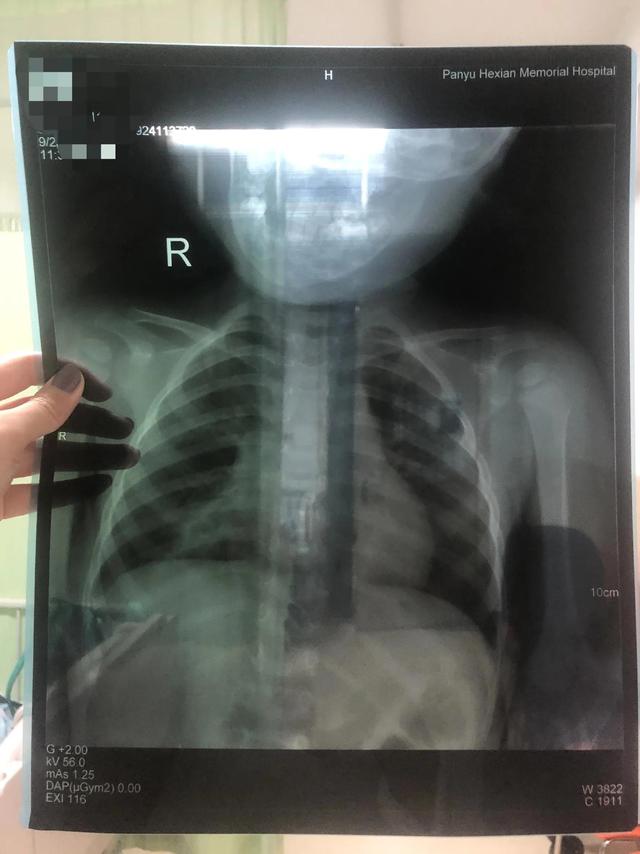

24号早上精神不咋滴就带去了其它医院看,这天没有发烧。结果医生验血拍胸片,结果出来要住院。下午打了点滴晚上回家精神好多了。吃喝拉撒正常,就是喘气声音大。